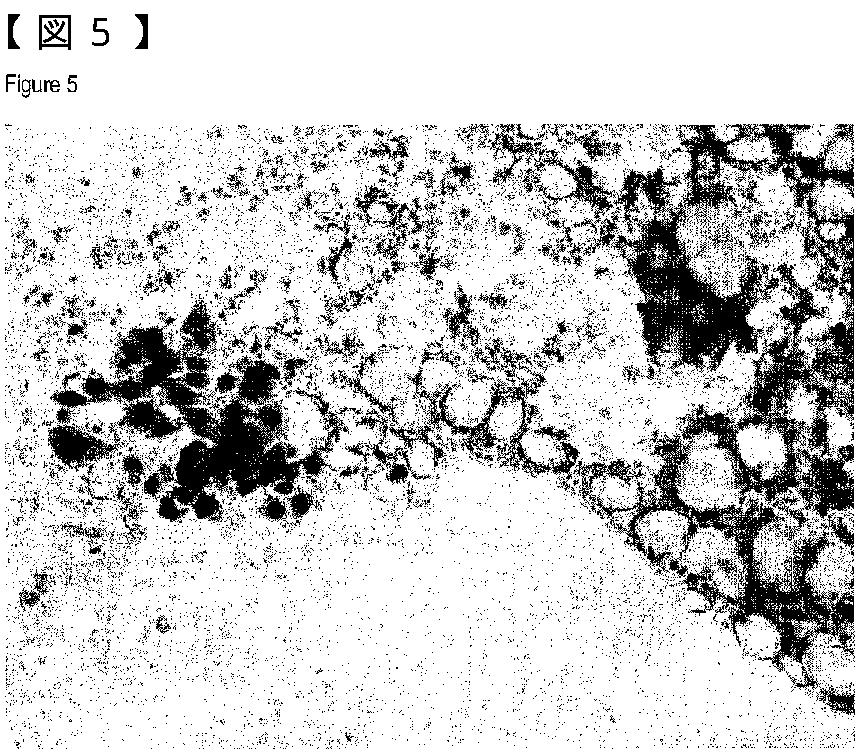

異形成と新生物病巣または前新生物病巣を区別するための方法